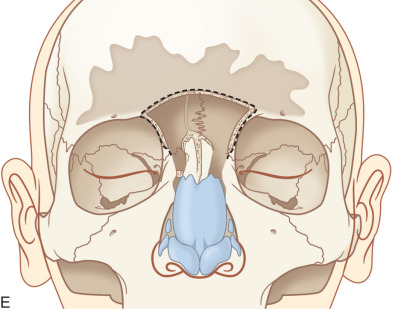

A transnasal endoscopic frontal sinusotomy (or Draf III procedure) is commonly used for management of chronic frontal sinusitis, mucoceles, frontal sinus trauma, and frontal sinus tumors. It provides access to the frontal recess as well as the anterior and posterior table of the frontal sinus. The procedure begins with an endoscopic ethmoidectomy and identification of the ethmoid skull base and lamina papyracea ( Fig. 1.7.12A ). Utilizing angled endoscopes (30, 45, or 70 degree depending on surgeon preference) and through cutting instrumentation, the floor, posterior wall, and roof of the agger nasi cell are removed. The frontal recess has now been dissected and an endoscopic view of the frontal sinus is achieved. The same procedure is then performed on the contralateral side until the bilateral frontal sinus ostia are visible. A 2 × 2 cm superior septectomy is then performed to gain bilateral access to the floor of the frontal sinus ( Fig. 1.7.12B ). The posterior limit of this window should align with the anterior aspect of the middle turbinate. The septal window is lowered until the opposite frontal recess and upper half of the opposing middle turbinate is visible. The septal mucosa is harvested and preserved as it may later be used for mucosal grafting of the exposed bone of the frontal beak. Utilizing a high-speed, angled 4 mm diamond bur, the bone of the septum is removed to identify the floor of the frontal sinus ( Fig. 1.7.12C ). The posterior limit of this dissection is the first olfactory neuron. The axilla of the middle turbinate (i.e., frontal process of the maxilla) is demucosalized and drilling proceeds from lateral to medial, removing the bone of the axilla and identifying the periosteum of the underlying skin ( Fig. 1.7.12D ). This marks the lateral limit of the dissection. The floor of the frontal sinus is then removed to create a large horseshoe-shaped neostium. The nasofrontal beak is thinned utilizing a 70 degree bur and 30 degree endoscope. The frontal intersinus septum is partially removed to create a median drainage pathway for the frontal sinus ( Fig. 1.7.12E ). The exposed bone of the frontal beak may be left bare, dressed with Silastic sheeting, or grafted with septal mucosa harvested from the creation of the septal window.